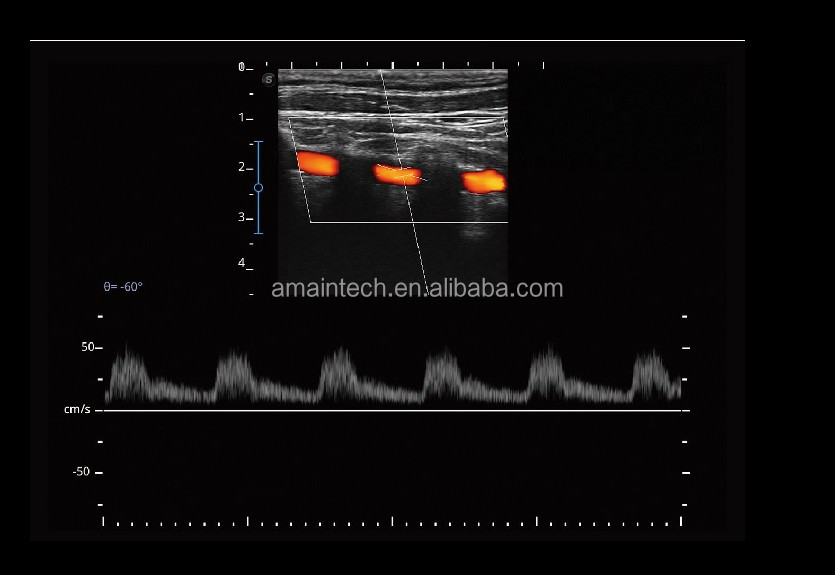

- Wide-ScanWith wide-scan, the ultrasound image can be enlarged when performing a real time scan when using linear or convex probes, for a larger, more complete view of large lesions.

With real-time panoramic, you can acquire an extended field of view for large organ or long vessel for easy measurement and diagnostic efficiency.

- Vis-NeedleVis-Needle is realized by ultrasound beam steering and deflection. It improves visualization of the needle location in the tissue to minimize harm to the surrounding tissue, increasing the initial

- Screen ZoomScreen zoom on E2 PRO enables the user to zoom in on the ultrasound image without fear of signal loss and gives a high resolution, zoomed in image so it is easier to see small details for a confident diagnosis and increased workflow. success rate and lowering the risk for needle puncture